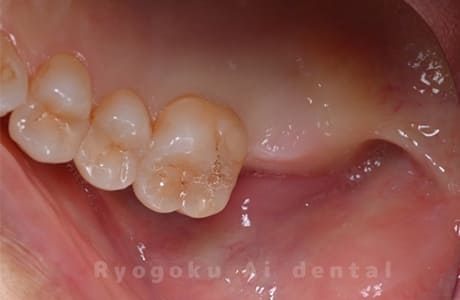

Case27

-

重度カリエス

歯牙移植咬合面術前 -

移植する親知らず

歯牙移植術直後咬合面

歯牙移植術後咬合面

歯牙移植術前側面

歯牙移植術中側面

歯牙移植術後側面

部分矯正術前咬合面

部分矯正術中咬合面

部分矯正術後咬合面

部分矯正術前側面

部分矯正術中側面

部分矯正術後側面

- 原因

- 重度カリエス

- 治療内容

- 自家歯牙移植、部分矯正

- 治療費用

- 220,000円(移植費用)

110,000円(部分矯正費用)

虫歯が大きく、保存不可能となった歯を上の親知らずと交換する自家歯牙移植を行いました。移植歯が小ぶりであったため、部分矯正を行い問題なく噛み合い、経過良好です。